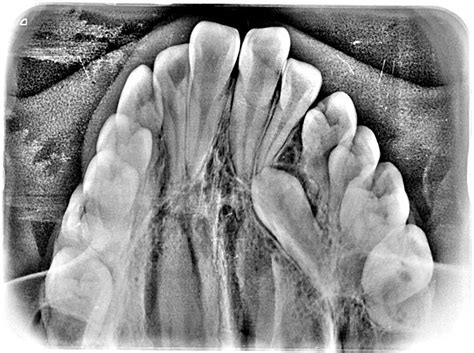

Figura 3 Fotografías intraorales pretratamiento. Vista oclusal.

La paciente ya ha iniciado la segunda fase de recambio de la dentición mixta, existiendo caries oclusodistal en 64, origen de un absceso que fistuliza a este nivel por vestibular, posible caries palatina en 26 y oclusomesial a nivel de 74. Ambos primeros molares superiores presentan sendas obturaciones oclusales. La relación molar es de Clase II, completa en el lado derecho e incompleta en el lado izquierdo, estando aumentados el resalte y la sobremordida. La oclusión en relación céntrica mandibular es coincidente con la máxima intercuspidación. Existe una ligera discrepancia de líneas medias, estando la línea media inferior levemente desplazada hacia la derecha con respecto a la superior. Los incisivos superiores aparecen diastemados, intuyéndose una discrepancia oseodentaria positiva en la arcada superior, mientras que, por el contrario, la arcada inferior evidencia una clara discrepancia oseodentaria negativa (figs. 2 y 3).

Figura 7A Vista oclusal de modelos pretratamiento.

Modelo superior Observamos una forma de arcada parabólica, con maxilar comprimido, incisivos superiores diastemados y mesiolinguorrotación de ambos primeros molares superiores (fig. 7A).

Modelo inferior La arcada describe una curva catenaria, con falta de espacio en la región de incisivos inferiores, que se encuentran apiñados. La discrepancia oseodentaria inferior, estimada en función del percentil 75 de las tablas de Moyers, es de -6,6 mm (fig. 7A).

Modelos en máxima intercuspidación Existe una relación molar de Clase II bilateral, siendo completa en el lado derecho e incompleta en el lado izquierdo. La línea media inferior se desvía 1,5 mm hacia la derecha con respecto a la línea media superior. El resalte está aumentado, siendo de +11 mm. Podemos calificar la sobremordida como completa o de 3/3 (fig. 7B).